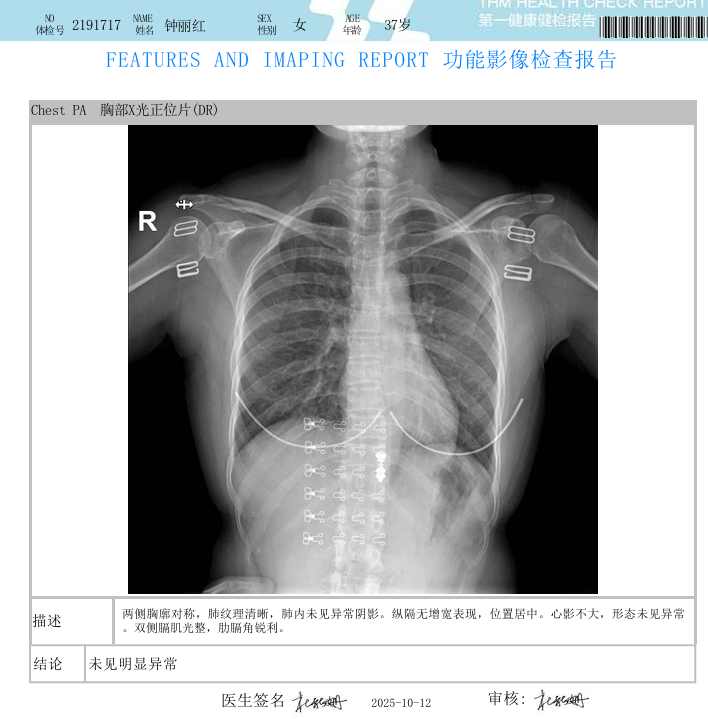

钟丽红